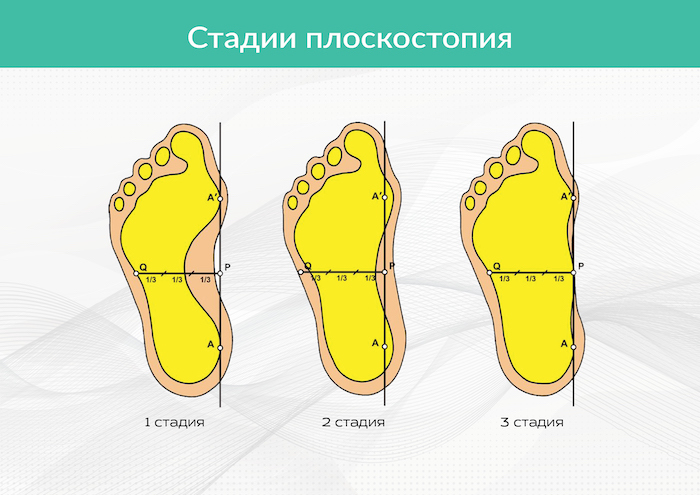

Стадии и симптомы

Симптоматика плоскостопия по стадиям:

- Первая стадия. Незначительная деформация стопы, но уже заметная невооруженным глазом. При продольном плоскостопии высота свода более 2,5 см, угол — 140°. При поперечном плоскостопии угол между I и II плюсневыми костями — 10°, угол отклонения большого пальца — 20°. Наблюдается изменение походки. При ходьбе или длительном стоянии довольно быстро появляется боль, усталость, стопы отекают.

- Вторая стадия. Плоскостопие прогрессирует. При продольном высота свода снижается до 1,8 см и меньше, угол увеличивается до 155°, при поперечном угол между I и II плюсневыми костями — 15°, угол отклонения большого пальца — 30°. При ходьбе человек постоянно испытывает боль, причем не только в ступнях, но и в коленях. Передвигаться трудно.

- Третья. Сильная деформация стопы. Свод почти полностью опущен. Ходить некомфортно — сразу же возникает боль. Болят не только ступни, но и позвоночник в районе поясницы, и даже голова. Наблюдается сильный отек голеней и ступней. При поперечном плоскостопии угол между I и II плюсневыми костями — 20°, угол отклонения большого пальца — 40°.

Рис. 1. Определение степени плоскостопия на плантографе (снимки).